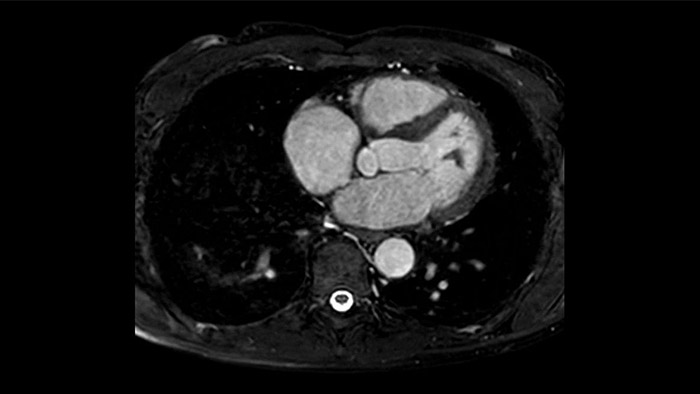

Diagnostic and prognostic utility of cardiac MR is increasing. Assess the anatomy and function of the heart using cine acquisitions, acquire information about perfusion and viability of the cardiac tissue, visualise potential edema with black blood sequence, access and even quantify tissue characterisation with CardiacQuant.

IntelliSpace Portal MR Caas5,6 4D Flow post-processing solution enables generation of 3D volume reconstructions, to visualise and evaluate blood flow in cardiovascular structures, including heart valves, chambers, and vessels, based on cardiovascular MR 4D Flow imaging.